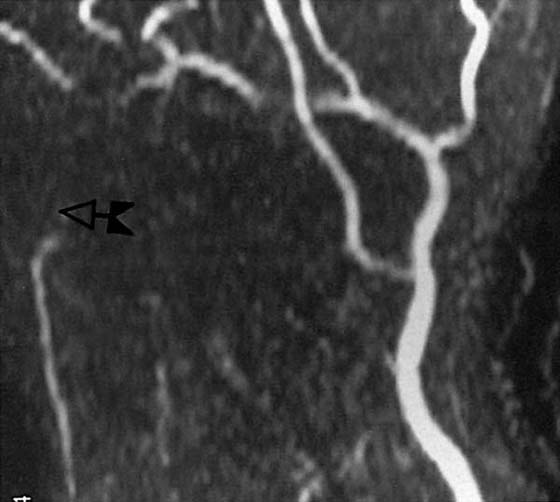

MRA is another tool that can easily demonstrate vascular abnormalities. MRA provides detailed information about the anatomy of the small vessels that constitute the carpal arches.23 MRA is noninvasive because it does not require the use of IV contrast material (Figs. 13-22 and 13-23, both online). Rather, it relies on the property of blood flow, and special pulsed sequences are used to enhance the fluid within the vessels.21

images

Figure 13-22 Magnetic resonance angiogram of a normal radial (curved arrow) and ulnar (straight arrow) artery.

Figure 13-23 Magnetic resonance (MR) angiogram demonstrating ulnar artery thrombosis (left). (Compare with normal MR angiogram in Figure 13-22.)